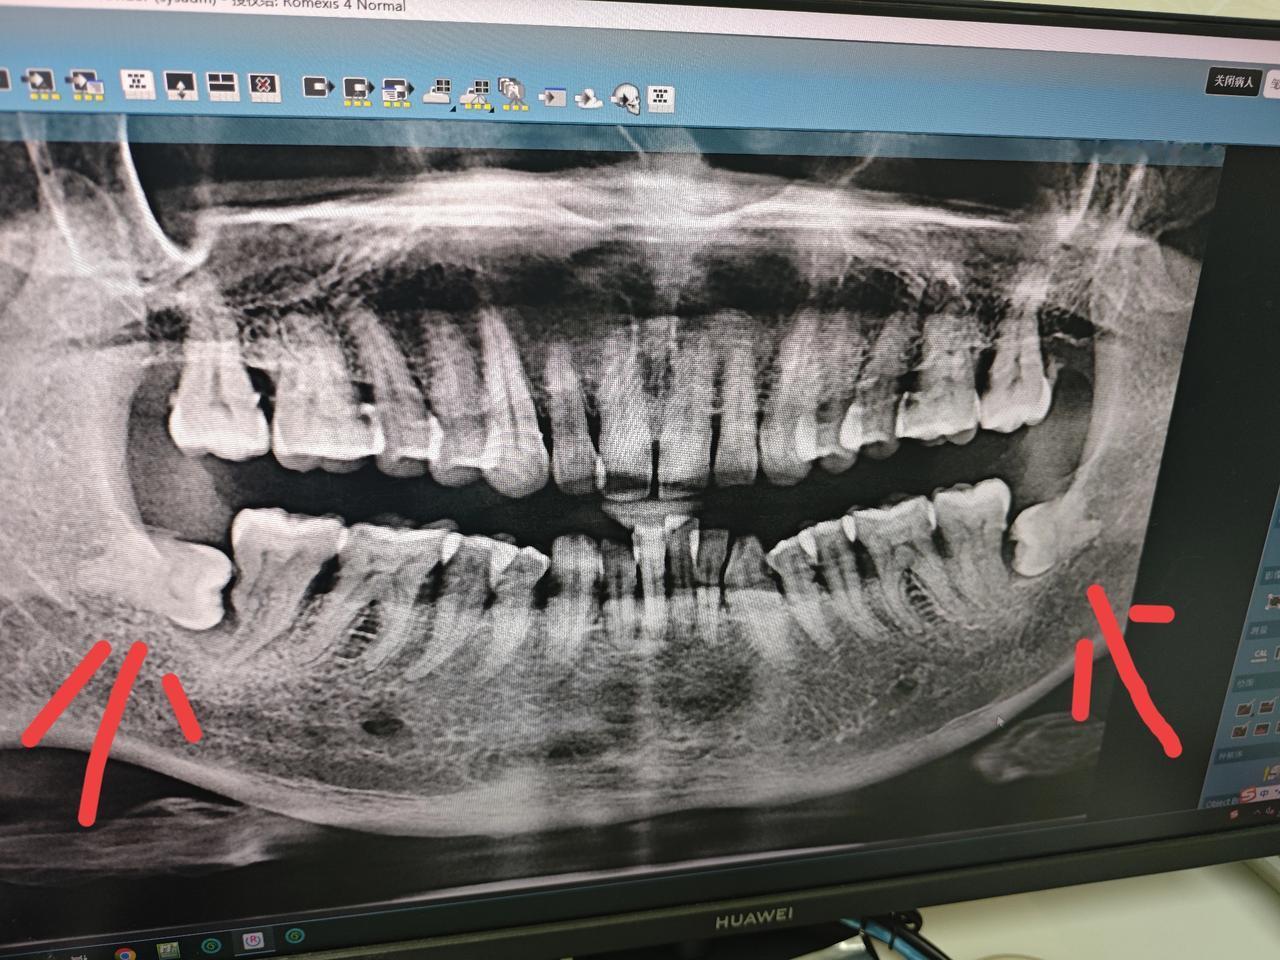

哎呀,牙齿痛了五天了,真是让我痛苦难忍。每次咬东西都钻心的痛,吃消炎药也丝毫没有缓解症状。每天只能靠止痛片来暂时缓解疼痛,但是效果并不理想。 牙医说可能是智齿发炎,建议我尽快拔除智齿。但是拔牙需要全身麻醉,我害怕手术,所以一直没有去做。朋友们有没有好的办法来缓解我的牙痛呢?有什么自然疗法或者替代疗法可以推荐吗?求大家帮助,让我尽快找到解决办法,不要再受这牙痛的折磨了。